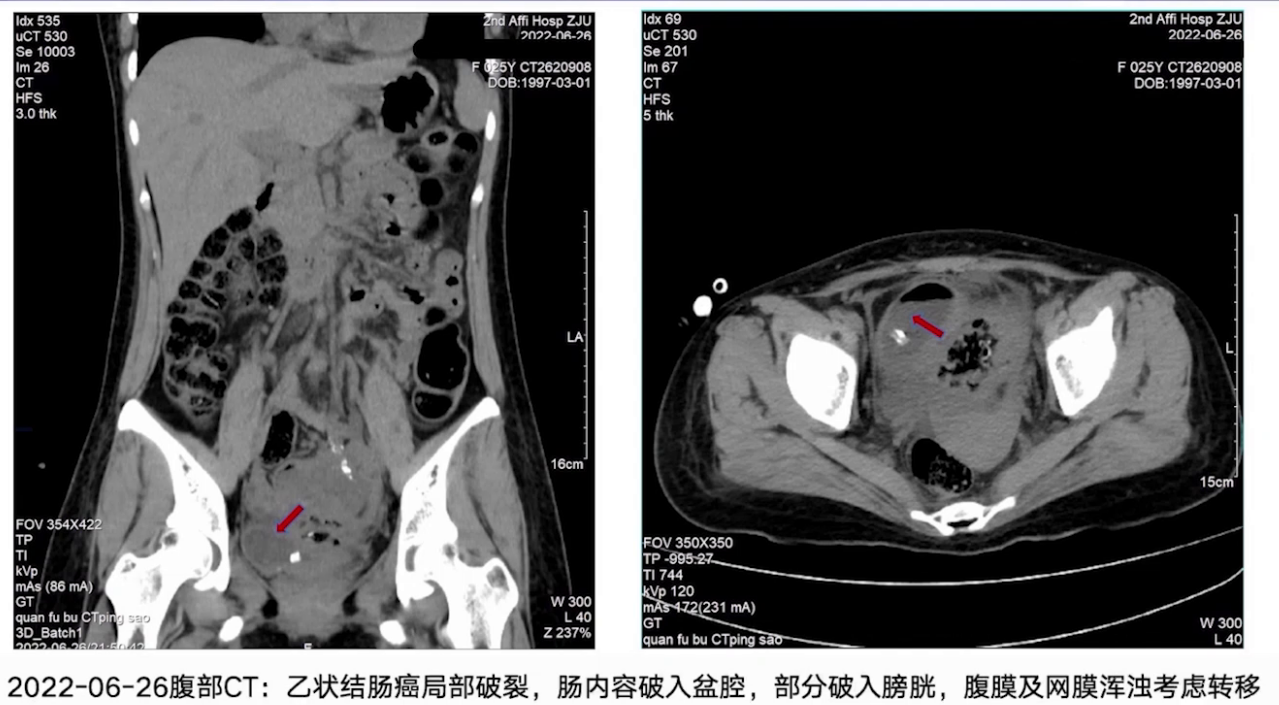

6月23日,患者出现会阴部不适,尿道及阴道排出粪水样液体,直肠MRI提示乙状结肠癌侵犯膀胱、子宫前壁及阴道上段,侵犯两侧盆壁及左侧卵巢,伴肠梗阻;CT提示乙状结肠癌局部破裂,肠内容物破入盆腔,部分破入膀胱,腹膜及网膜浑浊,考虑转移。